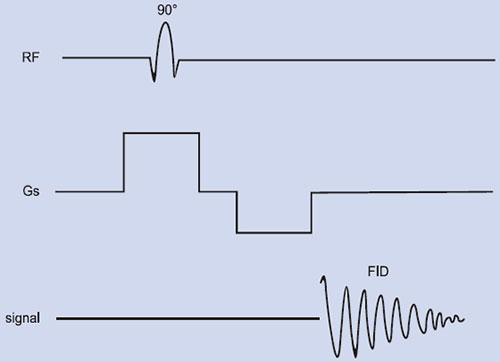

Depth Resolved Spectroscopy (DRESS)

DRESS sequence shown in Figure 1.10 was developed by Bottomley et al59 is the first spatial localization technique employing magnetic field gradients and was successfully used to acquire localized 31P and 1H spectra from humans and animals. In this method, a single slice is excited by applying a slice selection gradient to the plane of the surface coil with a frequency selective RF excitation pulse to provide depth resolution. The observed volume is the intersection of the excited slice and the sensitive volume of the coil, and is approximately a thick disc. Spatial localization depends critically on the excitation pulse and the surface coil used for detection. In DRESS, the sensitivity reduces as a function of the distance from the cylindrical axis of the surface coil51. For observation of a deep organ, signals from the surface regions can be suppressed effectively but sensitivity of DRESS sequence is directly related to the depth of the selective pulse that poses a great limitation. Another problem with DRESS is that significant loss of signal occurs for metabolites with short T2 due to short delay of a few milliseconds 24between excitation and detection necessitated by the application of a gradient-refocusing lobe for acquisition.